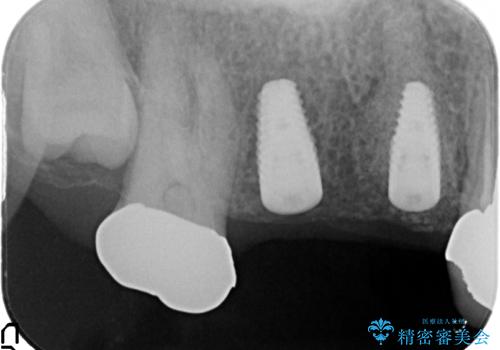

右上の567ブリッジを外したところ、右上5は歯根破折により保存不可能だったため、右上56部にインプラントを埋入し欠損補綴を行いました。

また右上5部に関しては抜歯時に歯槽堤保存術(抜歯窩に人工骨の填入を行う手術)を行い、骨の欠損を最小限に止めています。

当院では主にストローマンという種類のインプラントを治療に用いています。

ストローマンは世界的にもNo1のシェアを誇り、骨との適合にも優れたインプラントです。